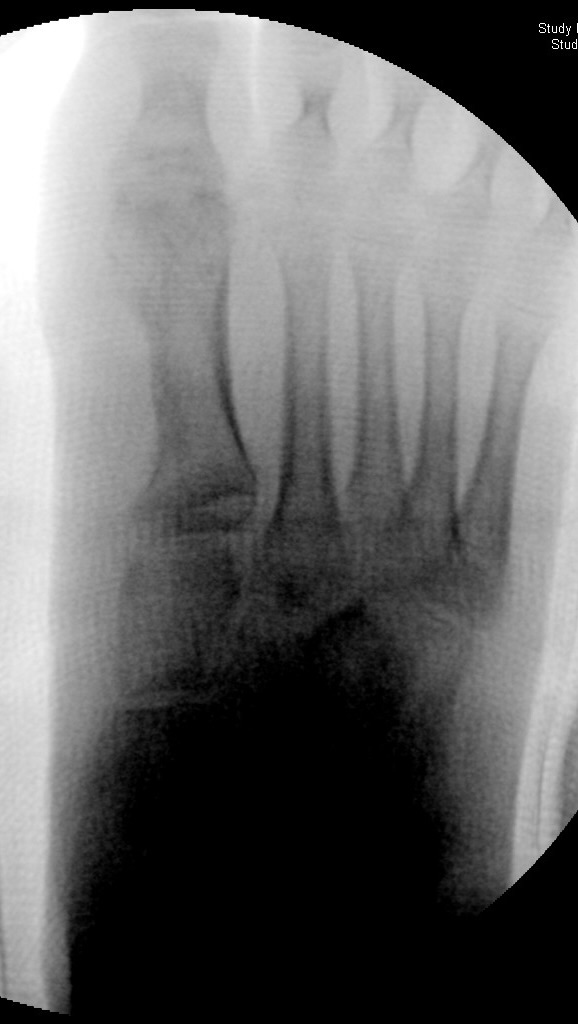

In der Regel bestehen aktive Wachstumsfugen bei Mädchen bis zum 12. und bei Jungen bis zum 14. Lebensjahr, mit Abweichungen von einem Jahr nach unten und nach oben. Präzise Informationen unter anderem darüber gibt das präoperative Röntgenbild (Abb. 2).

Abb. 2 a-c: offene Wachstumsfugen MT I Basis und Zehen (a), teilweise geöffnete Wachstumsfugen (b) und geschlossene Wachstumsfugen (c).

Zum Lesen der Bildbeschreibung und zur Vollansicht bitte die Bilder anklicken. Bilder: A. Helmers.

Die erforderlichen Osteotomien sind daher dem Fugenverlauf anzupassen, diese sind unbedingt zu respektieren. Wird eine Wachstumsfuge versehentlich mit der Fräse verletzt, kann durch partiellen oder kompletten Fugenverschluss ein Fehlwachstum provoziert werden. Achsabweichungen oder ein Wachstumstopp der betroffenen Region können die Folge sein. Offene Wachstumsfugen begrenzen die Osteotomieausrichtung besonders im Bereich des dorsalen Calcaneus, der Metatarsale I Basis und der IV. oder V. Zehe im End- und Mittelglied.